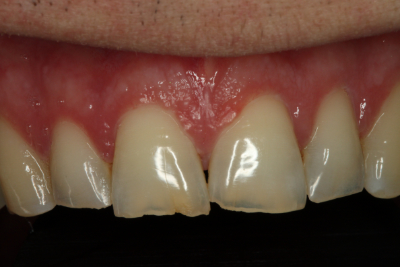

二次元評価から、咬合不安定性の徴候は明らかでした。 ダレンは、切歯縁が非常に薄く、欠け、透明になりつつあるほどでした。 上顎前歯の舌側にはほとんど棚が装着されており、機能的な包絡線が制限されていることが示唆されました。 また、前歯だけでなく後歯にも象牙質への摩耗があり、前歯はクラス1の可動性を持っていました。

審美的には、彼の上顎切歯縁はわずかに垂直方向に欠損しており長さを伸ばす必要がありました。 ダレンは咬合平面がわずかにカントしていましたが、本人はその矯正には興味がありませんでした。 下顎切歯面やアーチフォームも改善が必要でした。